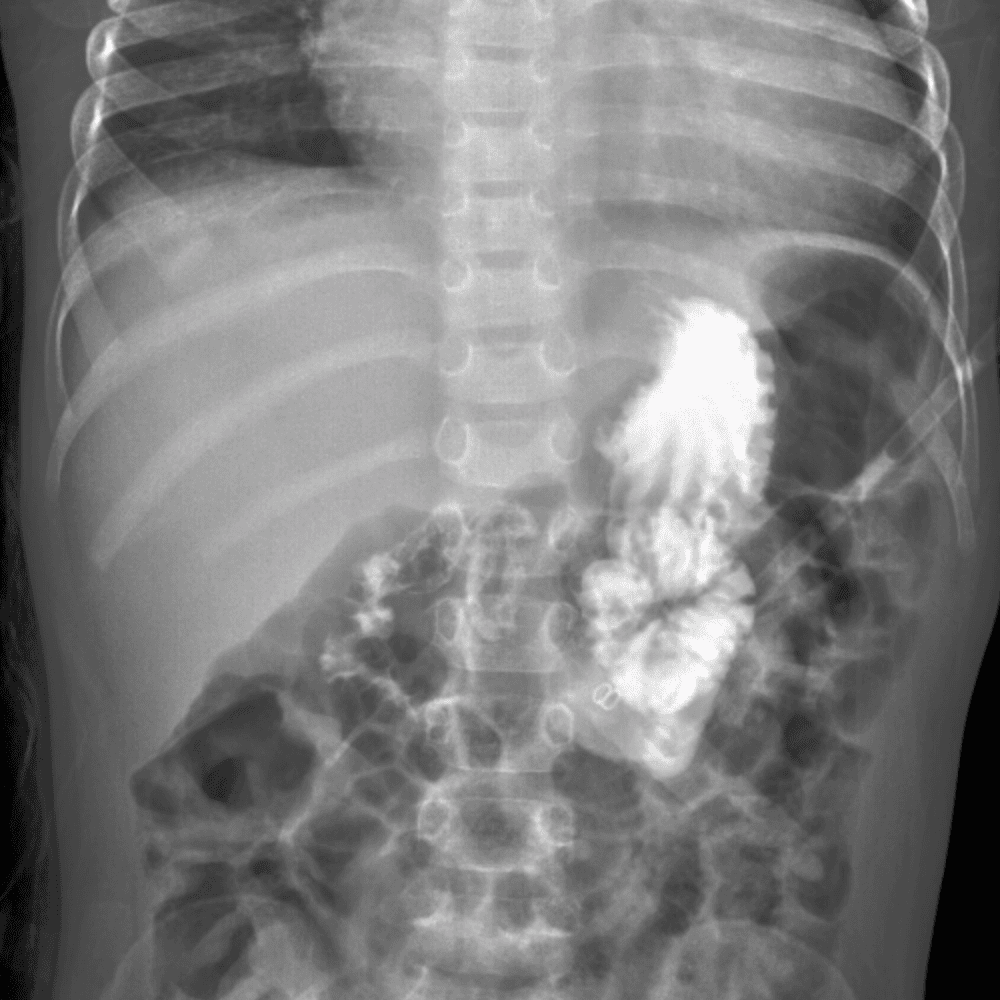

Peds Abdomen

Practice

Simulates call by including subtle or difficult cases and some normals.

30 cases